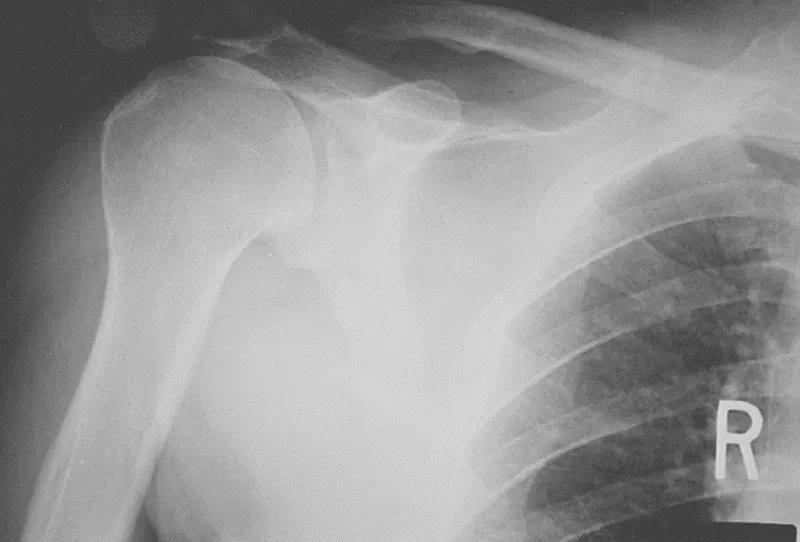

三、影像学检查1、X线检查X线检查用来评估肩峰形态,肱骨头和肩盂的关系,以及除外其他疾病。

图15 a.正常肩关节 b.肩峰撞击

图16 巨大肩袖损伤,肩峰下间隙<9mm